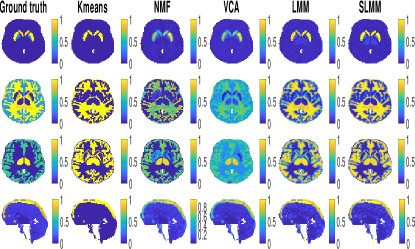

• The dynamic PET phantom has been first linearly unmixed using the N-FINDR [38] and SUnSAL [39] algorithms to select the ground-truth non-specific factor TAC 𝐦2,,𝐦Ksubscript𝐦2subscript𝐦𝐾\mathbf{m}_{2},...,\mathbf{m}_{K} and factor proportions 𝐚1,,𝐚Nsubscript𝐚1subscript𝐚𝑁\mathbf{a}_{1},\ldots,\mathbf{a}_{N}, respectively. These factor TACs and corresponding factor proportion maps are depicted in Fig. 4 (left) and Fig. 5 (left), respectively.

Refer to caption

Figure 4: Factor proportion maps of the 15th time-frame obtained for SNR=15dB corresponding to the specific gray matter, white matter, gray matter and blood, from top to bottom. The first 3 lines show a transaxial view while the last one shows a sagittal view. All images are in the same scale in [0,1]01[0,1]

The algorithms have been applied to 202020 different realizations of the noise to get reliable performance measures. Table II presents the NMSE averaged over these realizations for all algorithms and variables of interest while Table III presents their corresponding variances. The factor proportion maps recovered by the compared algorithms are shown in Fig. 4. Each row corresponds to a specific factor: SBF, white matter factor, non-specific gray matter factor, blood factor (from top to bottom, respectively). The six columns contain the factor proportion maps of the ground truth, and those estimated by K-means, NMF, VCA, LMM and the proposed SLMM (from left to right, respectively). A visual comparison suggests that the factor proportion maps obtained with LMM and SLMM are more consistent with the expected localization of each factor in the brain than VCA. Meanwhile, they are less noisy than the maps obtained by NMF. The estimated LMM and SLMM proportions maps are closer to the ground truth than both of them, particularly in the region affected by specific binding, as quantitatively shown in Table II. It can also be observed that the factor proportion maps obtained with the proposed SLMM approach present a higher contrast compared to LMM and other approaches, especially in the high-uptake region.

The maps of SLMM are also sharper compared to LMM. Additionally, it is also possible to see that NMF results for white matter are sharper but also more noisy than both LMM and SLMM approaches. However, for the specific gray matter, both LMM and SLMM approaches show sharper estimated factor proportion maps. Note that the sharpness of the factor proportions is not necessarily a good criterion of comparison. Indeed, factor analysis-based methods do expect to recover smooth maps that take into account the spilling part of partial volume effect, which is not considered within deconvolution. The aim of unmixing is not hard-clustering or classification.

The corresponding estimated factor TACs are shown in Fig. 5 where, for comparison purposes, the SBF depicted for SLMM is the empirical average over the whole set of spatially varying SBFs, as it is also the case for the SBF ground truth TACs. The best estimate of the SBF TAC seems to be obtained by the proposed SLMM approach, for which the TAC has been precisely recovered, as opposed to K-means, VCA and NMF. K-means provide the best estimate of the white matter TAC, closely followed by SLMM while NMF highly overestimates it. The best estimate of the non specific gray matter TAC has been obtained by VCA and NMF, even though it is slightly overestimated. It can be observed that SLMM and LMM have underestimated this factor TAC, which has been compensated with higher values in the corresponding factor proportion map. This underestimation results from the poor initialization of these algorithms by the K-means outputs. A more powerful initialization for the gray matter may provide better results. The factor TAC associated with blood is correctly estimated by SLMM, LMM, VCA and NMF.

The quantitative results in Table II confirm the preliminary findings drawn from the visual inspection of Fig. 4 and 5. The proposed method outperforms all the others for the estimation of 𝐌~1subscript~𝐌1\mathbf{\tilde{M}}_{1}, 𝐌2:Ksuperscript𝐌:2𝐾\mathbf{M}^{2:K} and 𝐚1subscript𝐚1\mathbf{a}_{1}. In particular, SLMM provides a very precise estimation of the mean SBF TAC with an NMSE of 0.9%percent0.90.9\%. In Fig. 5, the mean of the estimated SBF TACs 𝐦1,1,,𝐦1,Nsubscript𝐦11subscript𝐦1𝑁\mathbf{m}_{1,1},\ldots,\mathbf{m}_{1,N} is very close to the ground truth for LMM and SLMM but the the individual errors computed for each voxel demonstrate better performance obtained by SLMM. It also shows better results than K-means and NMF for 𝐀2:Ksubscript𝐀:2𝐾\mathbf{A}_{2:K}, even though it is less effective but still competitive when compared to LMM and VCA.